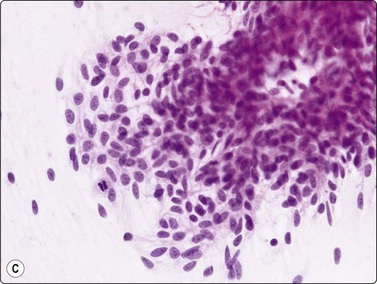

Fig. 9.1 Thymoma, lymphoepithelial

(A) Cohesive fragments of tumor tissue in a background of lymphoid cells (Pap, LP); (B) Cohesive cluster. Epithelial cells visible centrally Pap HP; (C) Cell block, indistinct epithelial cells (H&E, HP); (D) Cell block, reticular pattern of epithelial cell staining for AE1+3 keratins (IPOX, LP).

image image

Fig. 9.2 Thymoma, lymphoepithelial

(A) Less cohesive pattern with loose groups of epithelial cells (Pap, IP); (B) Loose group of epithelial cells with pale chromatin and conspicuous nucleoli (Pap, HP).

image

Fig. 9.3 Thymoma, lymphoepithelial

Tissue section; biphasic cell population (H&E, HP).

In the benign thymomas, the epithelial cells are usually cohesive (Figs 9.1, 9.5) but may also manifest a reduction in intercellular cohesion (Fig. 9.2). Epithelial cells are not immediately evident in the mixed tumors at low power but are discernible using the higher magnification.18,29,30 The epithelial cells are polygonal, oval, or spindle shaped with uniform to slightly irregular nuclear outlines possibly with cleaved or folded nuclei. Their nuclear chromatin is homogeneous, finely distributed and pale and, occasionally, small nucleoli are seen. Cell borders are indistinct, but nuclei are separated by moderate amounts of pale cytoplasm (Figs 9.2, 9.5). In one personally examined case of thymoma metastatic to lung, Hassall’s corpuscles were evident in the clumps of tumor cells (Fig. 9.4); this is a most unusual manifestation and will not be present in most thymomas. When there is a lymphoid population, the bimodal pattern enables one to make a virtually certain diagnosis.18,29,30 In pure epithelial or spindle cell forms, definitive diagnosis is more difficult, although in Dahlgren’s series29 most thymomas were diagnosed and in Tao’s 37 cases30 all FNAC diagnoses of thymoma were verified histologically. Ali and Erozan34 were able to diagnose all of their 14 cases using a combination of cytology, immunocytochemistry and clinical information, and Shin and Katz showed a high accuracy in a range of mediastinal lesions including 14 thymomas.35 Tao and others describe more variation in the degree of cohesion than we have seen, particularly in pure epithelial/nonspindle cell types.30 Overall, the most challenging and the most common in our experience are the lymphocyte-rich (type B1) thymomas, as the tumor cells may be obscured by the lymphocytes.